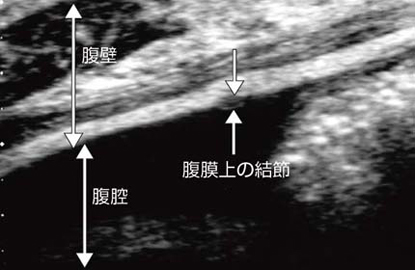

図13は,大腸がんの腹膜播種による腹膜上の結節である。これも同様に,他のモダリティで検出することは不可能に近い。

図13 大腸がん症例に見られた播種性の腹膜結節